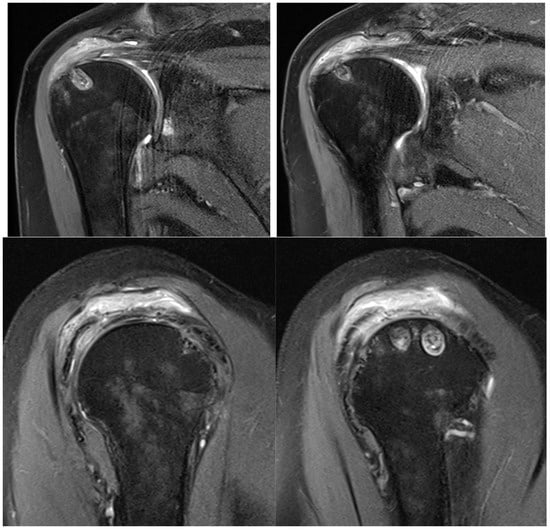

At six months after the surgery, a new MRI was performed, showing the reaction induced by the implant, with the progressive formation of tendon-like tissue (Figure 9).

Figure 9.

Postoperative MRI at 6 months after surgery, showing progressive formation of new tendon-like tissue with improvement of tendon thickness.

The effects of biological augmentation are evident in histologic studies and MRI. After 6 months, there is no histological evidence of the Regeneten implant remaining and the neotendon is indistinguishable from the native tendon on MRI, both in partial tears treated with isolated bioinductive repair and in full-thickness tears managed with complete augmented repair [5]. Schlegel et al. found that 87% of partial tears treated solely with bioinductive repair using Regeneten showed more than a 50% reduction in tear size in MRI after 24 months, along with a significant increase in tendon thickness. Additionally, no significant differences in clinical outcomes, tear healing, or tendon thickness were observed based on the location of the tear [7,19].

The subjective improvements and the improvements in the range of motion and tendon regeneration observed in this case are encouraging and suggest that the bioinductive implant may have contributed to enhanced healing. While a direct comparison with patients undergoing mechanical repair alone is not possible in this case report, the observed outcomes appear comparable to, or potentially better than, those reported in studies evaluating traditional repair techniques. Specifically, the patient achieved a near-full range of motion and a significant reduction in pain at 6 months post-surgery, which is a positive outcome. The observed outcomes in this case are consistent with the manufacturer’s reported data for the Regeneten implant, which indicate that the implant can promote tendon healing and improve clinical outcomes in patients with rotator cuff tears. Specifically, Smith and Nephew reports that Regeneten reduced the size of partial-thickness rotator cuff tears by over 50% in all tear locations [7]. The positive results observed in this case further support the use of Regeneten for the augmentation of rotator cuff repair. However, further research is needed to directly compare the outcomes of bioinductive implants with mechanical repair alone and other augmentation techniques.